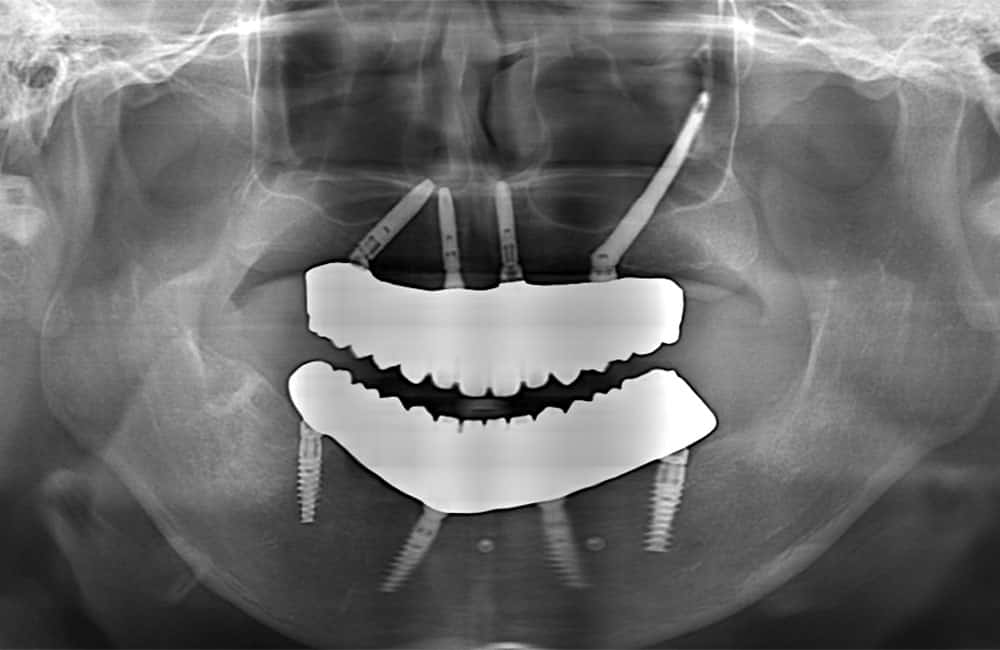

03All-on-4 Double Zygoma

前方、後方にザイゴマインプラントを用い上部構造を支える方法を、一般的にオールオンフォーダブルザイゴマやクアッドザイゴマと呼びます。上顎骨が大きく萎縮してしまったケースに対し、ザイゴマインプラントのみを用いる非常に難易度が高い治療法です。

症例